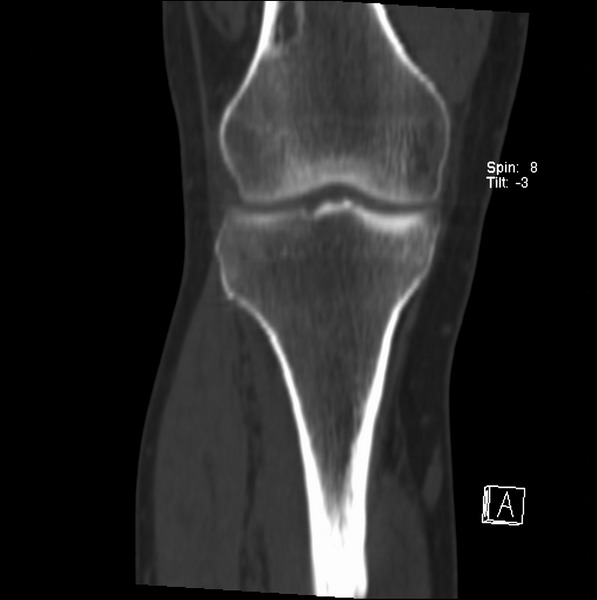

右侧膝关节疼痛一月

男、48

股骨下段、胫骨上段。

1、股骨干骺端病变考虑干骺端纤维性皮质缺损愈后(非骨化性纤维瘤)改变,胫骨近端内生骨瘤(或干骺端纤维性皮质缺损愈后改变);

2、骨关节炎,骨质增生,股骨外侧髁退变性囊肿(关节面软骨下囊肿);

1、股骨干骺端病变考虑干骺端纤维性皮质缺损愈后(非骨化性纤维瘤)改变,胫骨近端内生骨瘤;

股骨干骺端病变考虑非骨化性纤维瘤。